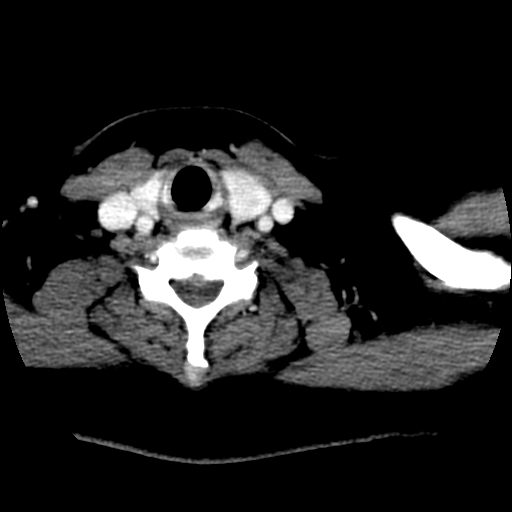

左右叶都有,峡部也受累,有钙化,考虑结甲可能性大。

甲状腺东西特异性不强,结节很小有很多是恶性,有的很怕人却是良性。